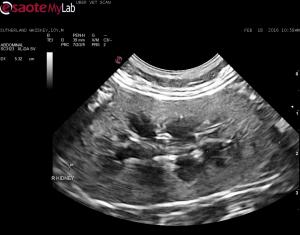

– kidneys are bilaterally enlarged (over 5cm) with hyperechoic coritices when compared to spleen but I don’t think they look abnormal otherwise and I have seen hyperechoic cortices in cats alot without disease (fat)

– no renal hypoechoic halo seen, no abdominal lymphadenopathy

Do I worry about these? recommend FNA? monitor via ultrasound?